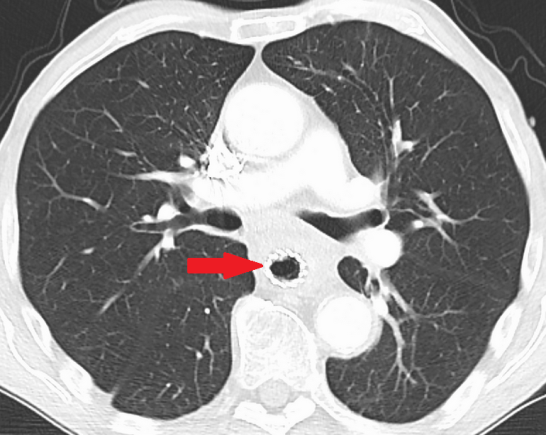

CT θώρακος — Αδενοκαρκίνωμα οισοφάγου με εξωαυλική επέκταση (Ευγενική παραχώρηση Dr. V. Penopoulos)